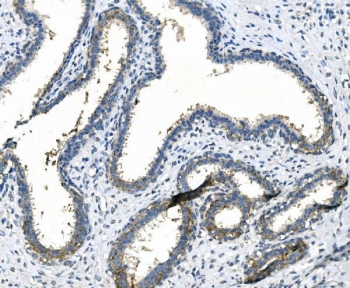

IHC staining of FFPE human rectal cancer with LPP antibody. HIER: boil tissue sections in pH8 EDTA for 20 min and allow to cool before testing.

IHC staining of FFPE rat intestine with LPP antibody. HIER: boil tissue sections in pH8 EDTA for 20 min and allow to cool before testing.